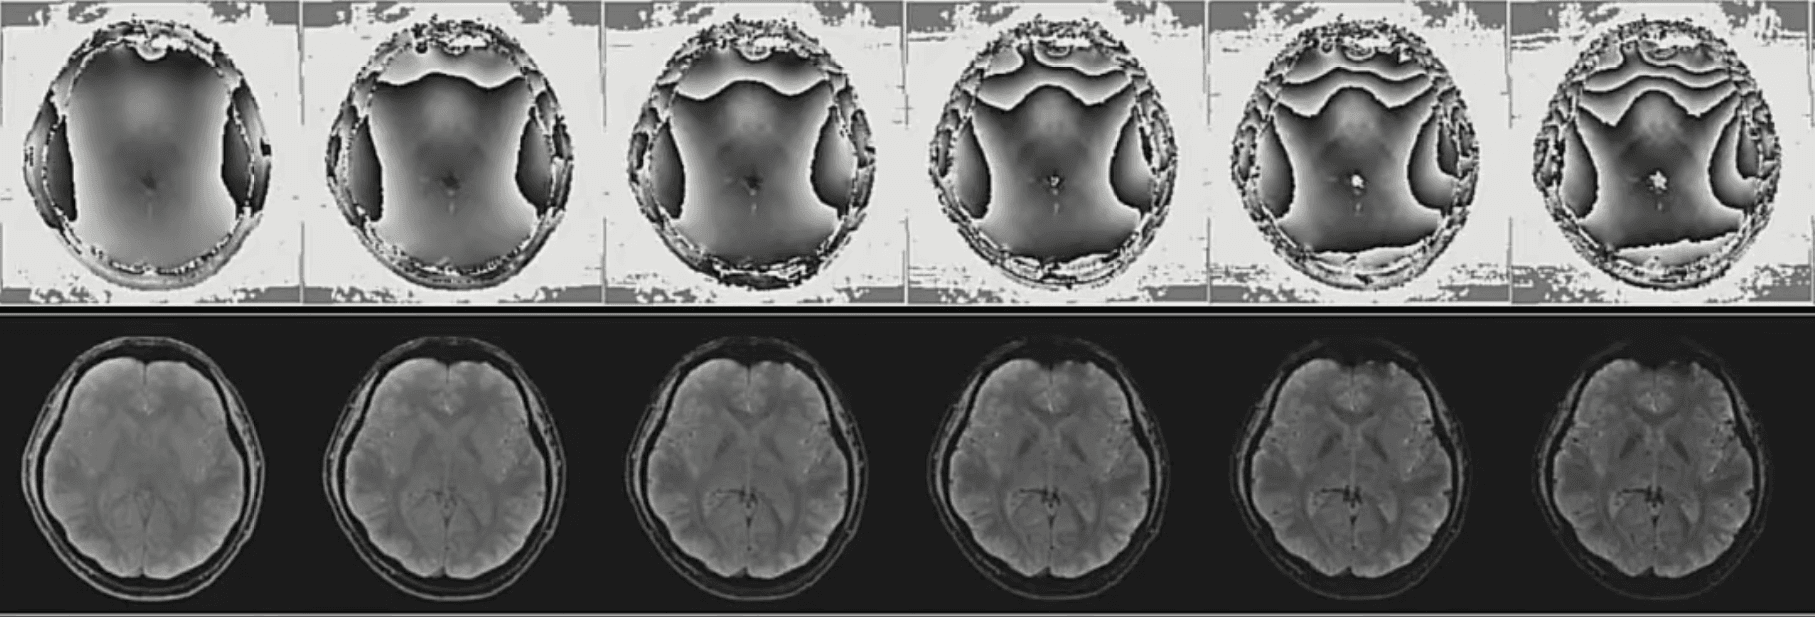

磁共振水脂分离技术:该技术基于脂肪和水的化学位移特性,水质子和脂肪质子的进动相位周期性出现反相位和同相位,利用同-反相位的扫描图像计算拟合出单独“水”或“脂肪”的分离图像,可用于低场磁共振,能同时得到物体的水像、脂像、同相位像和反相位像。在临床应用中,该技术所获得清晰准确的软骨细节图像可以极大提高疾病检查的准确度。同时,得到的水像和脂像可以计算出脂肪分数图像,以此反映脂肪密度、女性骨质疏松情况等